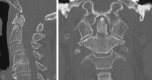

Fractures of the second cervical vertebra (C2, axis) are common in adult spine surgery. Those fractures occurring in younger adult patients are often associated with high-energy mechanism trauma, resulting in a "Hangman's Fracture." Management of these fractures is often successful with nonoperative means, though surgery may be needed in those fractures with greater displacement and injury to the C2-C3 disc. Older patients are more likely to sustain fractures of the odontoid process. The evidence supporting surgical management of these fractures is evolving, as there may be a mortality benefit to surgery. Regardless of treatment, longer-term mortality rates are high in this patient population, which should be discussed with the patient and family at the time of injury. Pediatric patients may suffer fractures of the axis, though differentiation of normal and pathologic findings is necessary and more difficult with the skeletally immature spine.